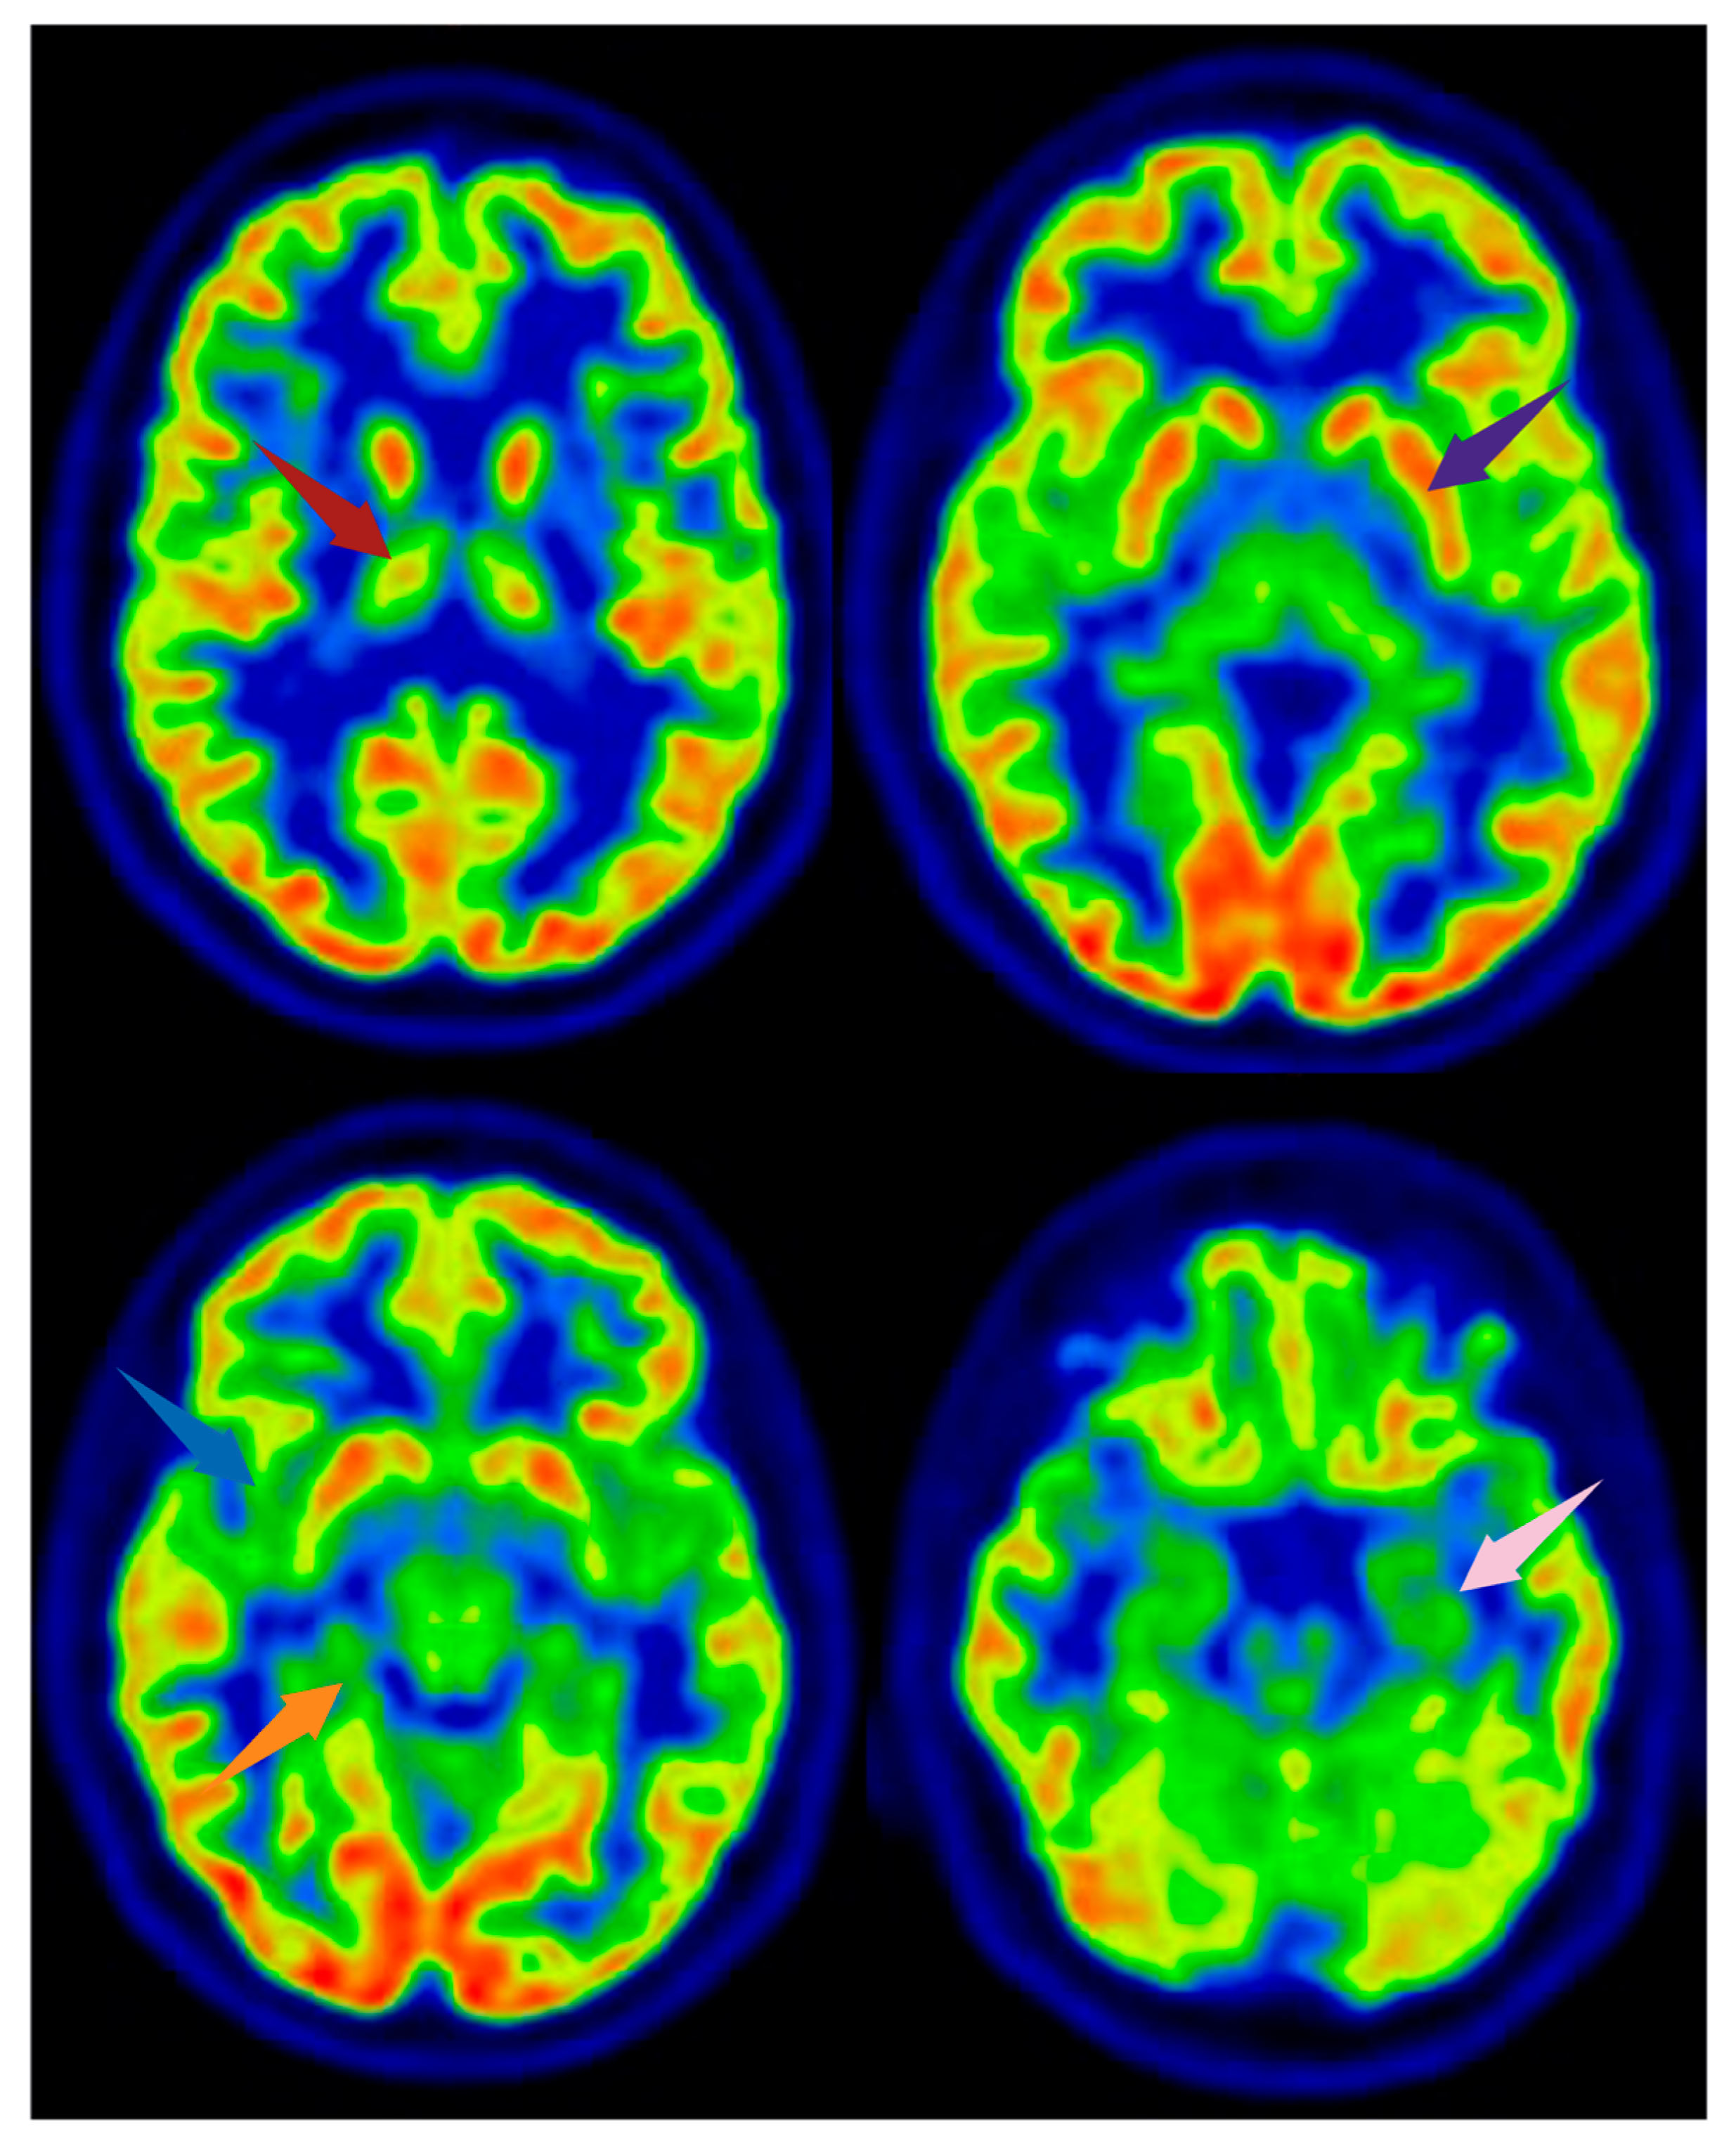

Figure 2. [18F]FDG PET images from a healthy subject. Arrows indicate brain regions commonly reported as altered in FMS, shown here for illustrative purposes. The subject depicted did not have FMS. Axial slices are shown. Red arrow: right thalamus; purple arrow: left lentiform nucleus; blue arrow: right insula; orange arrow: parahippocampal gyrus; pink arrow: medial temporal cortex. Image created using BioRender.com.

Several PET studies have investigated alterations in regional cerebral glucose metabolism in FMS patients using [18F]FDG. Most of the findings have been controversial, as they have failed to demonstrate any statistically significant difference in brain glucose metabolism between treatment-naïve FMS patients and healthy subjects [25,26] (Figure 2 and Figure 3).

The comparison of FMS patients with good and poor responses to medical pain reduction treatment revealed that different brain structures are involved in pain modulation in [18F]FDG PET studies [25,26]. It was found that poor responders show significantly greater metabolism in the left thalamus, bilateral lentiform nucleus, and right parahippocampal gyrus than good responders [27]. This is particularly interesting because an earlier study found that the same brain regions were involved in the analgesic effects of electroconvulsive therapy for FMS-related pain [28]. This effect has been linked to altered thalamic activity following transcranial direct current stimulation and complex changes in gray matter volume [29,30].

[18F]FDG PET scans have also revealed that the insular metabolic hypoactivity is associated with the development of hyperalgesia [31]. Peyron et al. have pointed out that the insular cortex as one of the regions most consistently activated by noxious stimuli related to intensity coding [32]. The insula is also a critical point in the interconnection of dopaminergic (DAergic) and gamma-aminobutyric acid (GABA) activity because GABAergic interneurons are involved in its DAergic modulation [33]. GABA greatly inhibits neuronal activity within the insula; thus, a reduction in insular GABAergic neurotransmission lowers the pain threshold and leads to the hyperalgesia observed in chronic pain conditions [27,34,35,36].

Presynaptic DA transporters (DATs), which remove DA from the synaptic cleft after phasic activation, also seem to play a role in pain modulation. Furthermore, one [18F]DOPA PET study has found that DA metabolism is significantly lower in FMS patients than in controls not only in pain cortex regions such as the brainstem, thalamus, and multiple areas of the limbic system, but also in the ventral tegmental area (VTA) [38] (Figure 2).